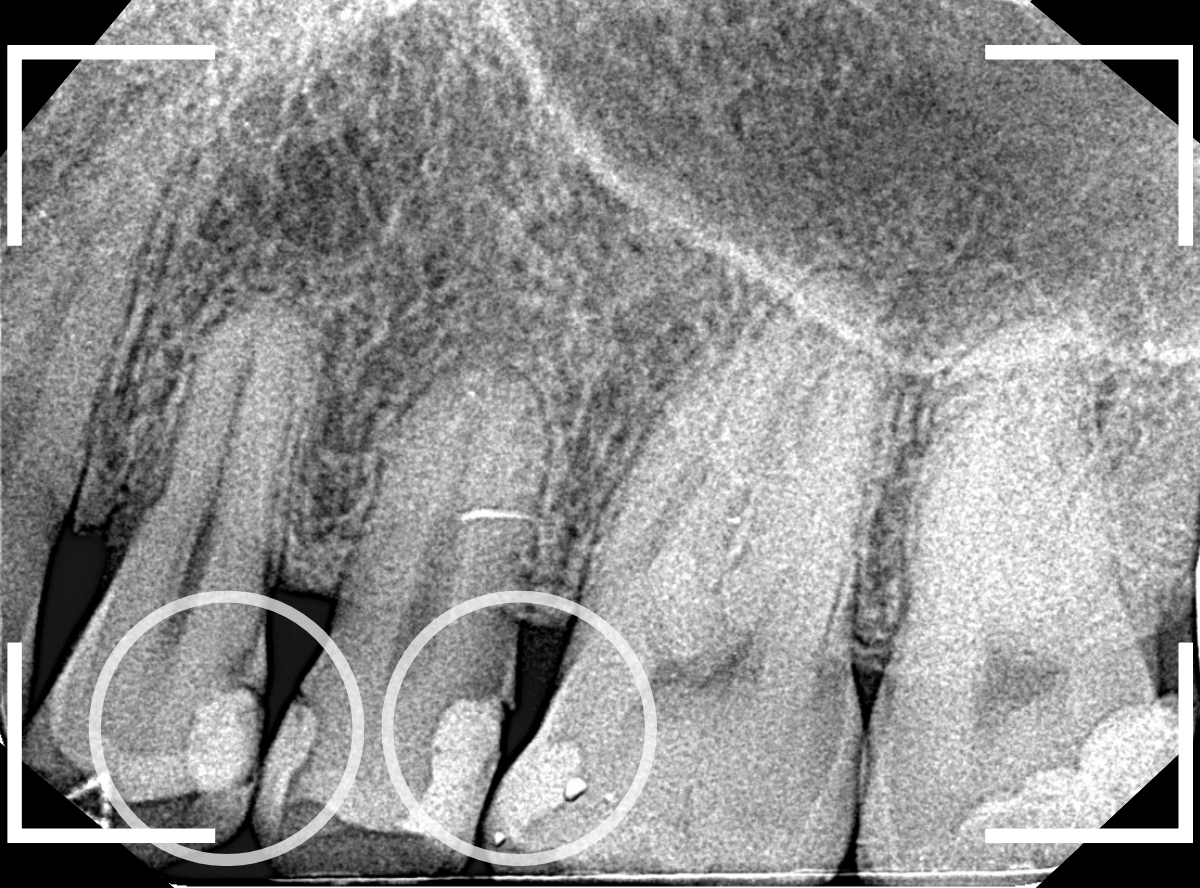

Case.17 歯の側面のレジンの中のわかりづらい虫歯

検診で、金属のつめ物のの中と、歯の側面に虫歯が見つかった方です。

まずは、手前(左)側の治療です。

こちらが、お口の中を見たところです。

〇部の中に虫歯があると思われます。

今回のように、金属のつめ物やレジン治療をしてある歯の側面の虫歯の診断はわかりづらく、難しいです。